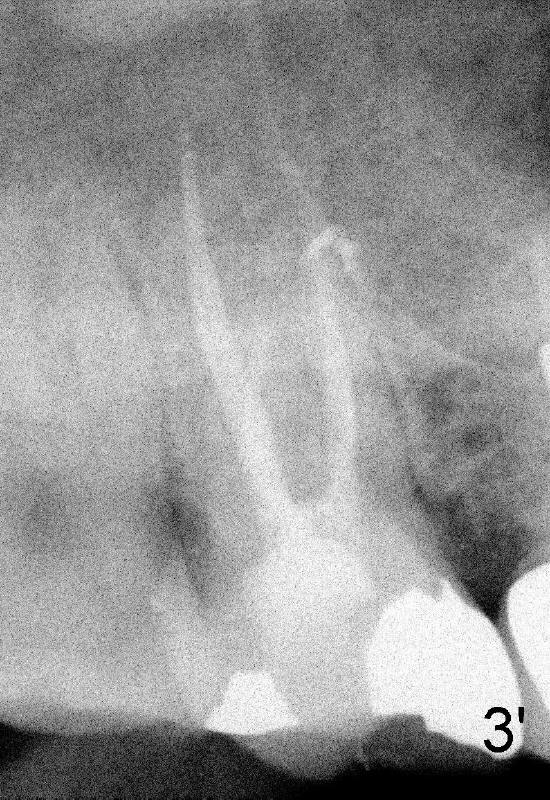

五十一岁Junita牙齿不好,右上有一个悬臂桥(图一’:5.6),她要找一位医生能解决她所有的牙科问题:右上7牙髓炎(图一’),右下,左下6植牙(图’四)。她最大问题是害怕牙科治疗,根管治疗中不太配合:牙胶尖插入后拍摄X光片,位置不对,没有显示根尖(图二’),最后根管充填效果尚可(图三’),疼痛没有了,病人的心被我们收买了,接着我们准备分期给右下,左下6植牙,但是她坚决反对,要求一次完成两个植牙,因为她非常怕痛,对钻耳环洞都害怕极了,做了一个耳环(图’四:箭头),再没有勇气回去做第二个。好了,明天做二个植牙,到时向大家汇报。这位胆小病人上战场时胆怯了,迟到一会儿,说她不愿意左右各做一个植牙,影响吃饭。由于右下近远中间隙比左下大些,我们先做右下植牙,回学术讨论园地